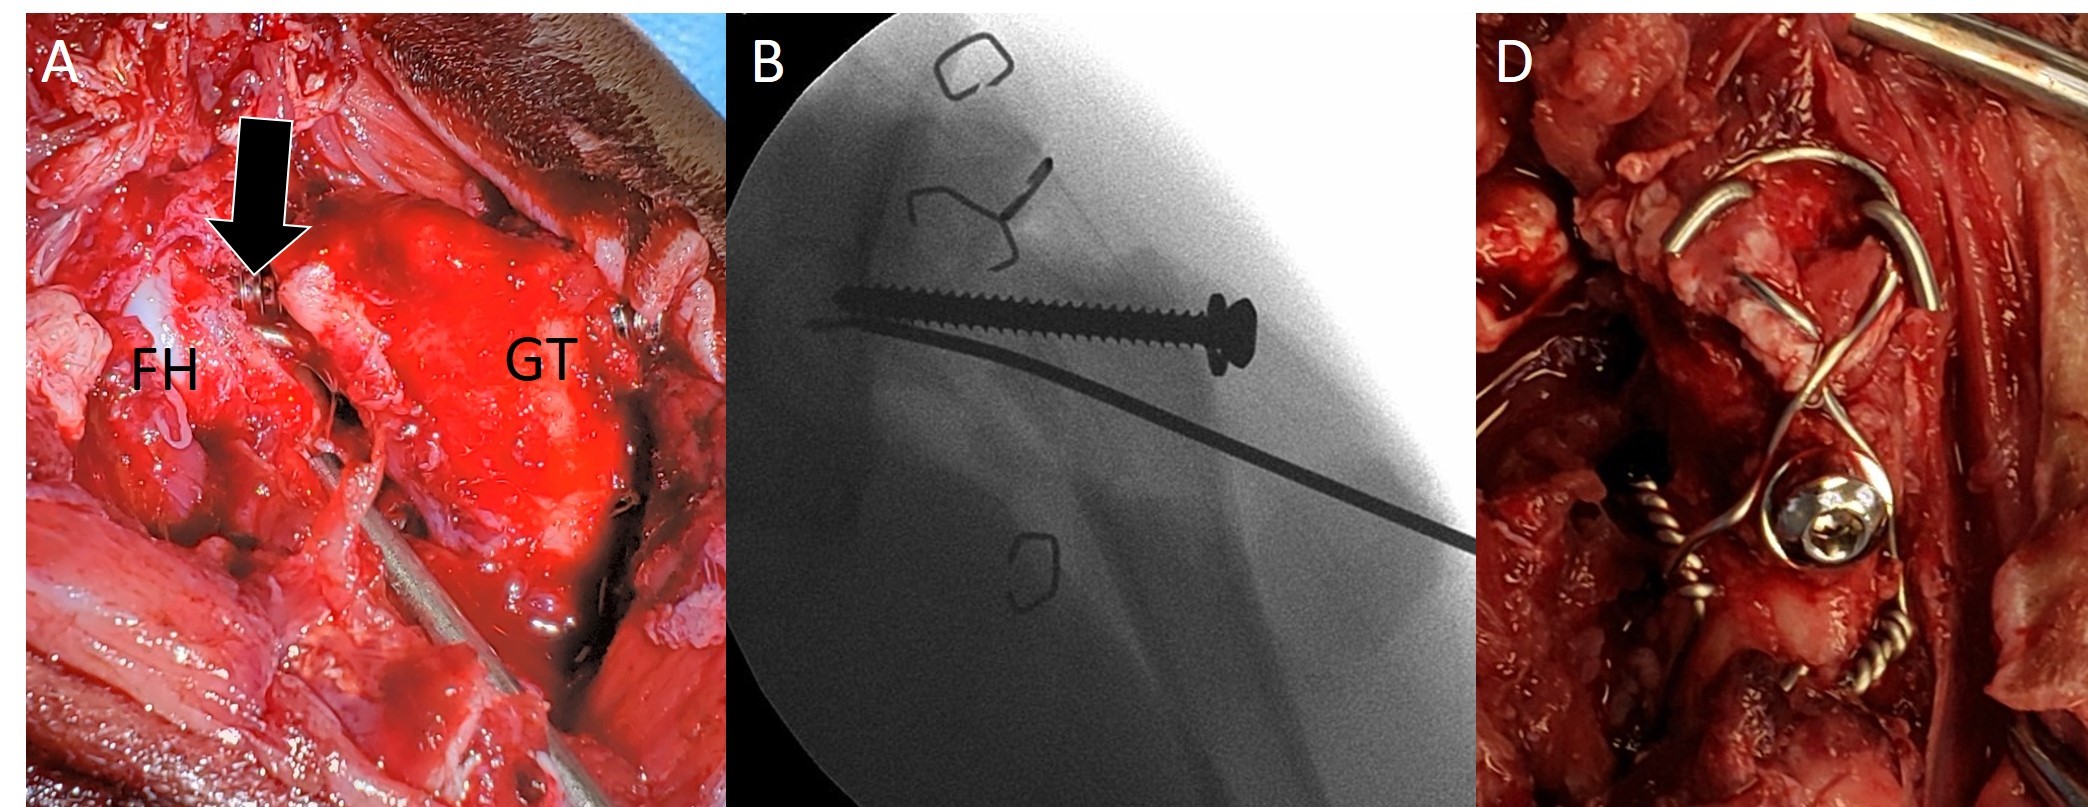

Presenting with a fractured femoral neck and additional avulsion fracture of the greater trochanter, the bobcat, if left untreated, likely would have had limited use of the limb due to nonfunctional malunion. Without treatment, the bobcat likely would have ended up in a zoo or similar facility; euthanasia was never an option. The rescue organization’s main goal is to recover injured wildlife and then release them—and all animals receive the same dedication and care, whether opossum, rat, or bobcat.

The treatment included placement of a screw with a washer and a pin to reestablish the femoral neck, and a tension band to secure the trochanter.

“His young age was the only reason this surgery was a success. During the procedure, I knew this was not going to look good on post-op radiographs. Indeed, when I saw those films, I was more or less convinced it would fall apart, especially knowing that this was a wild, energetic bobcat,” von Pfeil notes. “Only the dedicated care of Laura’s team—and the extremely good cooperation between us to stage the recovery process—allowed this injury to heal.”